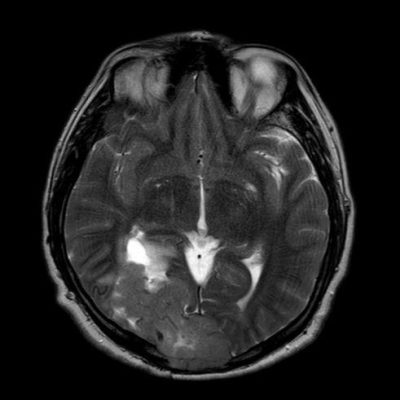

44 yaş, E

Baş ağrısı

hemorajik glioblastoma multiforme (GBM, WHO Grade 4)